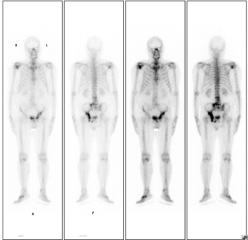

患者老年男性,因前列腺癌骨转移伴明显疼痛,于20228月行全身骨显像,后给予锶89及唑来膦酸等联合治疗,疼痛明显缓解,于20235月行全身骨显像复查,病灶明显减少、范围缩小、病灶活跃程度减低。